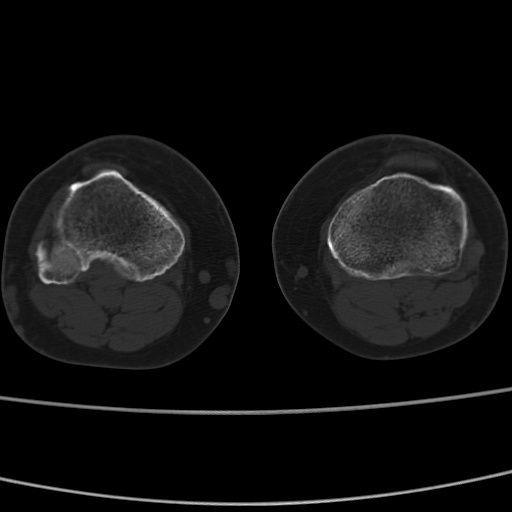

女性,50岁。【请提供患者临床症状体征】

胫骨后缘陈旧性骨折(是否有病史)

右膝关节退行性改变,关节游离鼠。

右膝关节退行性改变,滑膜黏液囊钙/骨化并游离。